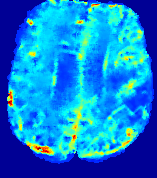

TimeSlice(i)(ii)(iii)(iv)(v)(vi)Refer to caption00555101010151515202020252525Refer to caption(a)(b)Refer to captionRefer to captionRefer to captionRefer to captionRefer to captionRefer to captionRefer to captionRefer to captionRefer to captionRefer to captionRefer to captionRefer to captionRefer to captionRefer to captionRefer to captionRefer to captionRefer to captionRefer to caption(a)(b)Refer to captionRefer to captionRefer to captionRefer to captionRefer to captionRefer to captionRefer to captionRefer to captionRefer to captionRefer to captionRefer to captionRefer to captionRefer to captionRefer to captionRefer to captionRefer to captionRefer to captionRefer to caption(a)(b)Refer to captionRefer to captionRefer to captionRefer to captionRefer to captionRefer to captionRefer to captionRefer to captionRefer to captionRefer to captionRefer to captionRefer to captionRefer to captionRefer to captionRefer to captionRefer to captionRefer to captionRefer to caption(a)(b)Refer to captionRefer to captionRefer to captionRefer to captionRefer to captionRefer to captionRefer to captionRefer to captionRefer to captionRefer to captionRefer to captionRefer to captionRefer to captionRefer to captionRefer to captionRefer to captionRefer to captionRefer to caption(a)(b)Refer to captionRefer to captionRefer to captionRefer to captionRefer to captionRefer to captionRefer to captionRefer to captionRefer to captionRefer to captionRefer to captionRefer to captionRefer to captionRefer to captionRefer to captionRefer to captionRefer to captionRefer to caption(a)(b)Refer to captionRefer to captionRefer to captionRefer to captionRefer to captionRefer to captionRefer to captionRefer to captionRefer to captionRefer to captionRefer to captionRefer to captionRefer to captionRefer to captionRefer to captionRefer to captionRefer to captionRefer to caption

Figure 6: Predicted concentration time series for the same patient shown in Fig. 4, where (i)-(vi) correspond to slices #1-6 respectively. Each grouped row displays (a) the measured concentration image sequences and (b) the predicted concentrations at corresponding time points.

3.2 Predicted CA Concentration

To better illustrate the prediction accuracy, and therefore the estimation accuracy of 𝐕𝐕{\bf V} and D𝐷{D}, of PIANO, we provide the corresponding predicted time-series of CA concentration images in Fig. 5 and Fig. 6 for the same patients in Fig. 3 and Fig. 4, respectively. We see that PIANO is capable of predicting the CA concentration given their initial state, indicating its ability to successfully capture 𝐕𝐕{\bf V} and D𝐷{D}. Note that although the concentration values for these two patients differ considerably, caused by the different total volume of injected CA, PIANO is still able to provide plausible estimates.